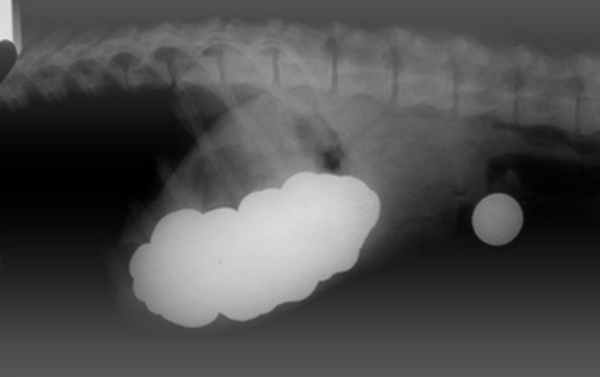

Диагностика инородных тел

Диагностика инородных тел пищевода и желудка включает в себя обязательное использование инструментальных методов, таких как: рентген, контрастная рентгенография пищевода и желудка, эзофагогастроскопия.

Существуют инородные тела рентгеноконтрастные – они визуализируются на рентгене, и не рентгеноконтрастные – они не визуализируются на рентгене (например, дерево). Дополнительное введение рентгеноконтрастных веществ (сульфат бария, йодсодержащие препараты), при проведении рентгена пищевода и желудка, позволяют в некоторых случаях определить не рентгеноконтрастные инородные тела (фото 1).

Наиболее объективной диагностикой является эндоскопический метод – эзофагогастроскопия. Инородное тело в пищеводе у собаки и у кошки можно определить с помощью эзофагогастроскопии и даже выявить последствия их пребывания в пищеводе и желудке, оценить состояние слизистой оболочки (фото 2, 3).

Особую проблему представляет собой хирургия пищевода грудного отдела. Операция проходит в грудной полости в условиях искусственной вентиляции лёгких. Для проведения подобного оперативного вмешательства необходимо чётко знать местоположение инородного тела в пищеводе, так как разное положение определяет место доступа в грудную полость. Для этого необходимо провести эзофагогастроскопию животному (фото 4,5,6,7).

Фото 6а, 6б, 6в: Инородное тело (игрушка) в желудке лабрадора